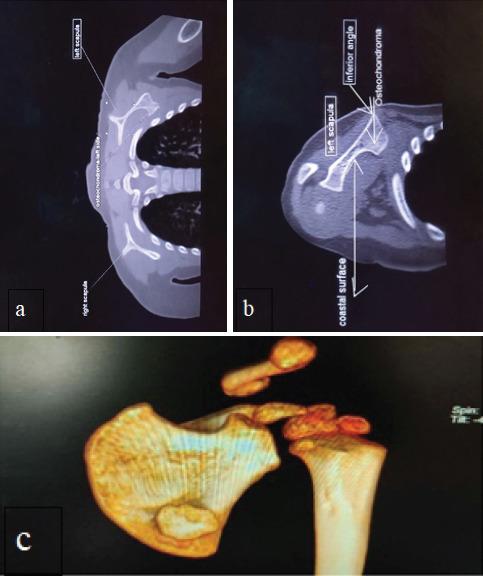

A 2-year-old male child presented with painless, immobile, and non-fluctuant swelling over the left scapular region, insidious in onset and progressive in nature. On examination, a non-tender, immobile swelling was palpable with a painless and unrestricted range of motion at the shoulder joint. After evaluating radiographs and CT scan, the patient was diagnosed to have a ventral scapular osteochondroma leading to pseudo-winging of the scapula.

一名2岁男童,左肩胛区出现无痛、固定且无波动感的肿胀,起病隐匿且呈进行性发展。检查时,可触及一个无压痛、固定的肿胀,肩关节活动范围无痛且不受限。经X线片和CT扫描评估后,该患者被诊断为腹侧肩胛骨软骨瘤导致肩胛骨假性翼状畸形。